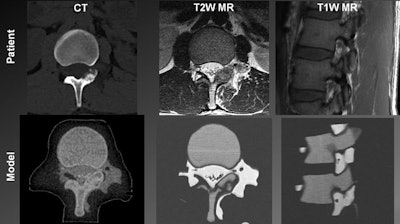

The researchers began creating the 3D-printed spinal models for the two patients with osteoblastomas by segmenting previously acquired images. They segmented the cortical bone, bone marrow, osteoblastoma, diaphragmatic crura, and aorta from prior CT scans; the bone marrow, crura, aorta, epidural and paraspinal fat, thecal sac, and spinal nerves from T2-weighted MR images; and the bone marrow and spinal nerve roots from T1-weighted MR images.

Next, the researchers combined the segmented portions of the CT scans with the segmented components of the MR images by aligning the identical structures found in both modalities, i.e., the bone marrow, crura, and aorta. They input this composite 3D model into a 3D printer capable of creating models using two different materials (Objet500 Connex 2, Stratasys).

The two base materials were a black rubber material with very low CT signal (FLX980) and a high-temperature material with medium MR signal and high CT signal (RGD525). Mixtures of these two materials provided individual tissues with distinct compositions visible on CT and MRI. The 3D printer encased the spinal model in a shell and filled the empty areas of the shell -- representing the fat tissue and cerebrospinal fluid -- with a glycerin-based support material.

A comparative analysis of images of the 3D-printed spinal model and patient anatomy revealed that all relevant tissues that are normally distinguishable on in vivo CT scans and MR images were also discernible on the scans and images of the spinal model. Each mixture of "biomimicking" materials also had a high enough contrast-to-noise ratio (greater than 5:1) to be sufficiently distinguishable on CT and MRI.